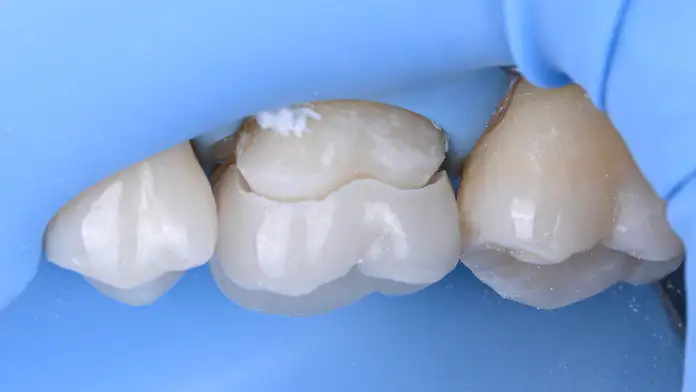

레진으로 치료하기에 범위가 넓은 경우, 보다 구조적인 안정성을 위해 사용할 수 있는 치료 방법입니다. 구강 외에서 정교하게 제작된 보철물을 접착하여, 구조적인 안정성과 저작 기능을 회복합니다.

힘을 많이 받는 치아의 뾰족한 부위(교두)가 손상되었거나, 균열(Crack)이 있어 파절 위험이 높은 경우 시행합니다. 크라운처럼 전체를 깎지 않고도 약해진 치아 윗부분을 보강하여, 치아가 쪼개지는 것을 예방하는 핵심적인 보존 술식입니다.

크라운에 비해 치아 삭제량을 극적으로 줄여주면서, 치아의 핵심 구조를 보존하는 고난도 보철 술식입니다. 치아의 수명을 연장하기 위한 생체 모방적(biomimetics) 접근법입니다.

간접 수복은 구강 외에서 수작업으로 보철물을 제작합니다. 정교하게 치아의 해부학적인 형태를 복원하고, 교합 관계를 회복시킵니다.

정밀하게 제작된 보철물은 경계부에서의 오차를 최소화하고, 내면의 적합을 최대화하는 방향으로 제작됩니다.